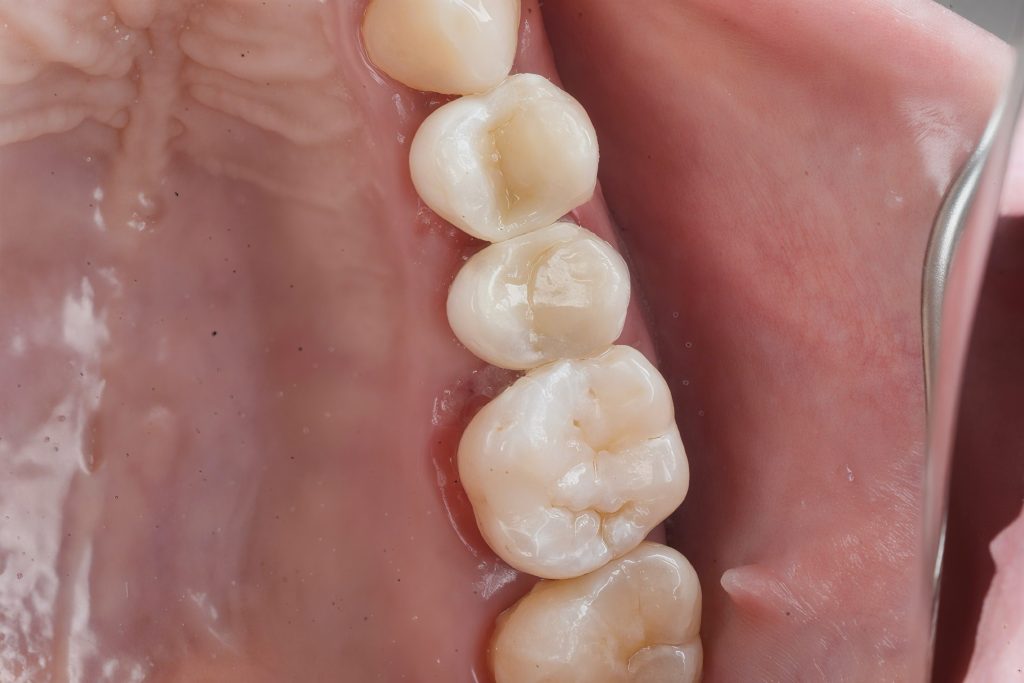

- Occlusal anatomy was sculpted with fine instruments under microscope visualization. (Fig. 6–8)

6. Finishing and Polishing

After polymerization, margins were refined using fine diamond burs and silicone polishers (Dentsply Enhance & PoGo). Final gloss was achieved, blending the restoration with natural enamel surface texture. (Fig. 9–10)

Fig. 8–9: Final anatomic layering and occlusal modeling under microscope.

Fig. 10: Completed restoration showing esthetic integration and functional harmony.